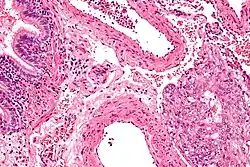

Der makroskopische Befund[5] ähnelt einem schweren Emphysem mit verbreiterten Alveolarsepten. Dadurch wird das Atmen für Patienten mit LAM immer schwerer und sie sind körperlich wenig belastbar. LAM verursacht bei einem Teil der Betroffenen auch Angiomyolipome der Nieren oder fibrotische Gewebeveränderungen im Bauchraum und vergrößerte Lymphknoten. Bei der Hälfte aller Betroffenen kommt es im Verlauf der Erkrankung zu schweren Symptomen wie Pneumothorax (Kollaps der Lunge) und bei circa 15 % der Frauen Chylothorax (Ansammlung von Lymphflüssigkeit im Pleuraspalt).

- ↑ Abbildung aus RadioGraphics ( des vom 27. September 2007 im Internet Archive) Info: Der Archivlink wurde automatisch eingesetzt und noch nicht geprüft. Bitte prüfe Original- und Archivlink gemäß Anleitung und entferne dann diesen Hinweis.